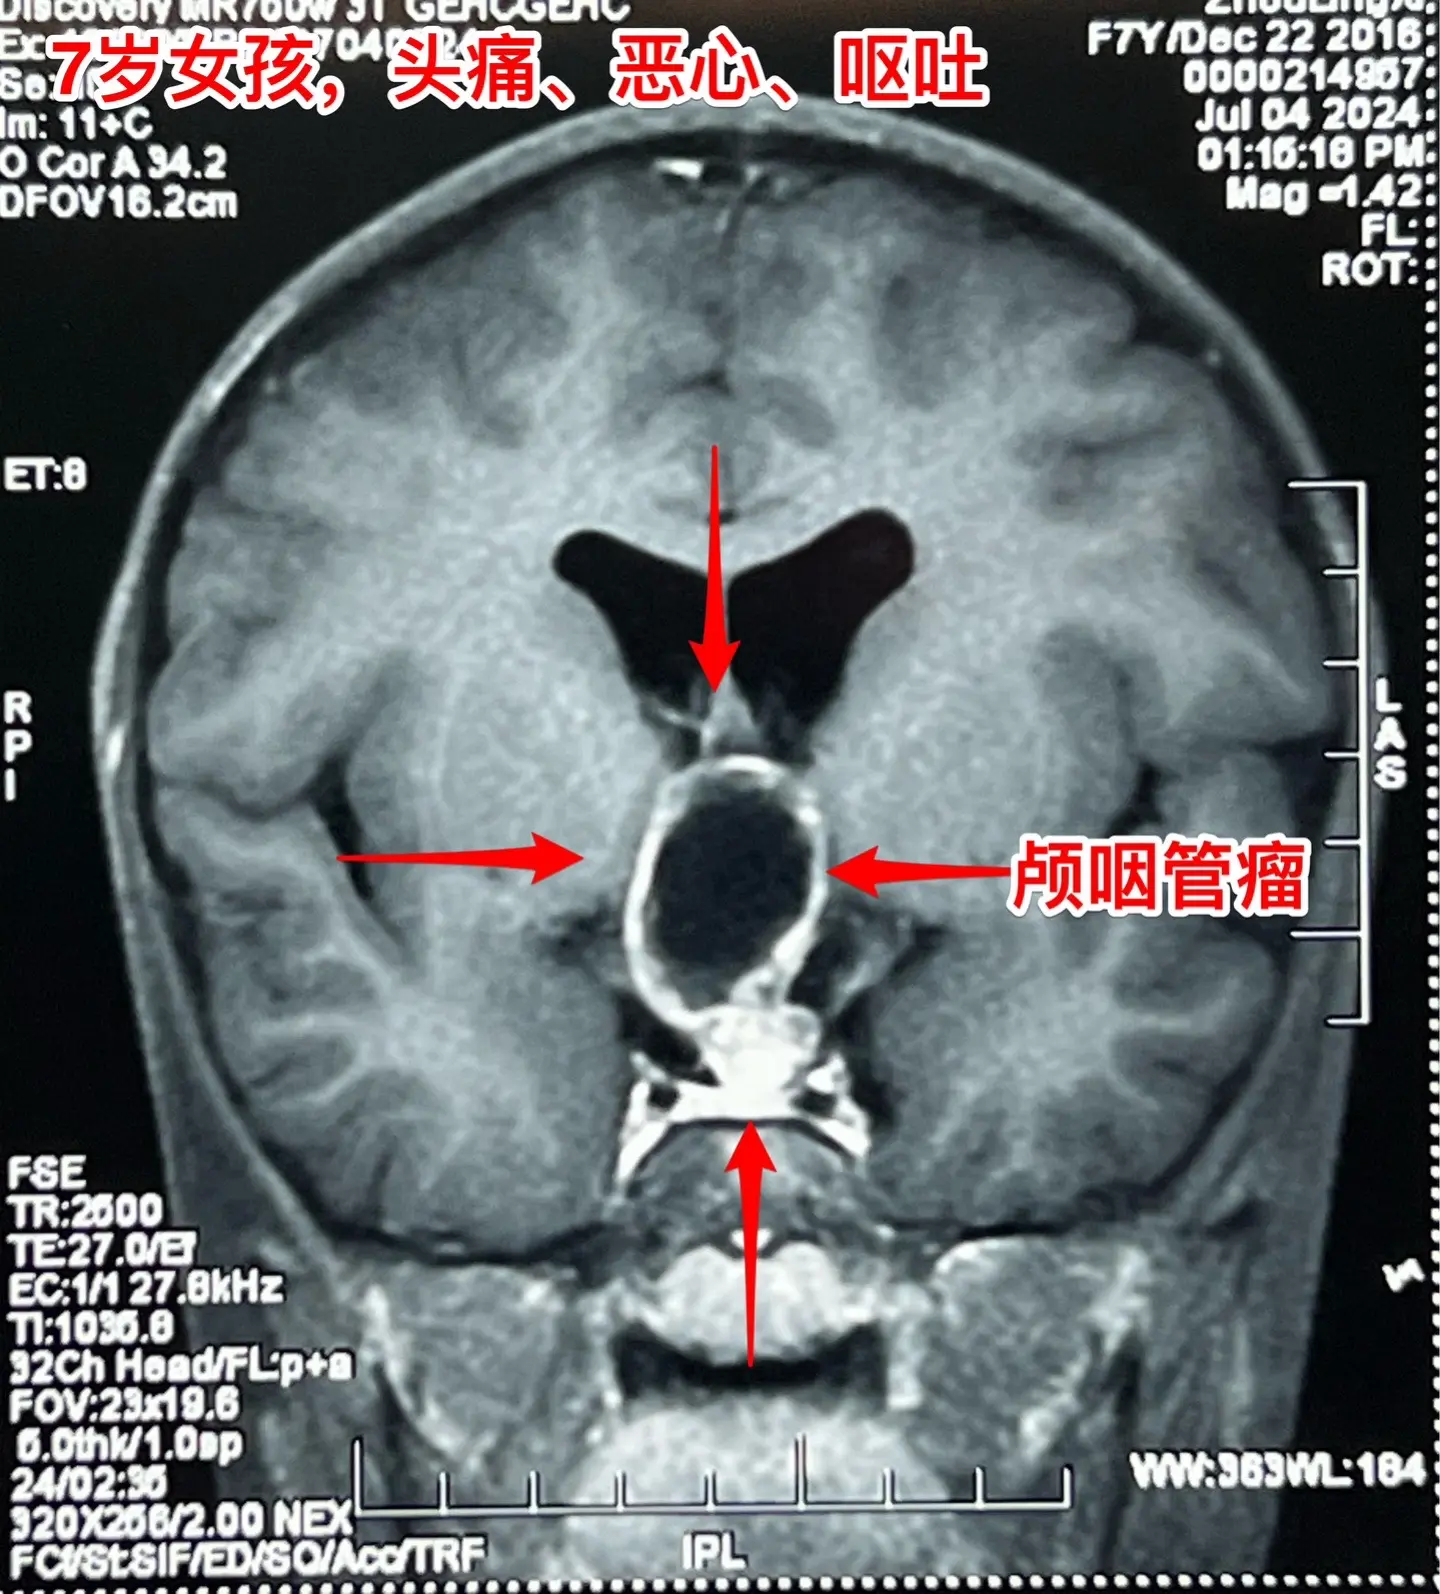

头痛、恶心、呕吐,是颅内高压症状!7岁江西上饶的小女孩,一个月前感头痛、恶心、呕吐。这是颅内高压的症状。他们到就近的医院就诊,作头部CT和磁共振,发现了颅咽管瘤,这个颅咽管瘤造成了梗阻性脑积水,颅内高压,所以小孩子出现头痛、呕吐症状。 根据头CT可以看见肿瘤内有钙化,可以确诊是典型的造釉细胞性颅咽管瘤。这样的肿瘤造成的脑积水,一般在切除肿瘤后就可以自愈,不需要专门作脑积水的手术。 2024年7月12日作了手术,肿瘤得到完全切除。 目前小孩子身体状况很好,快要出院了。